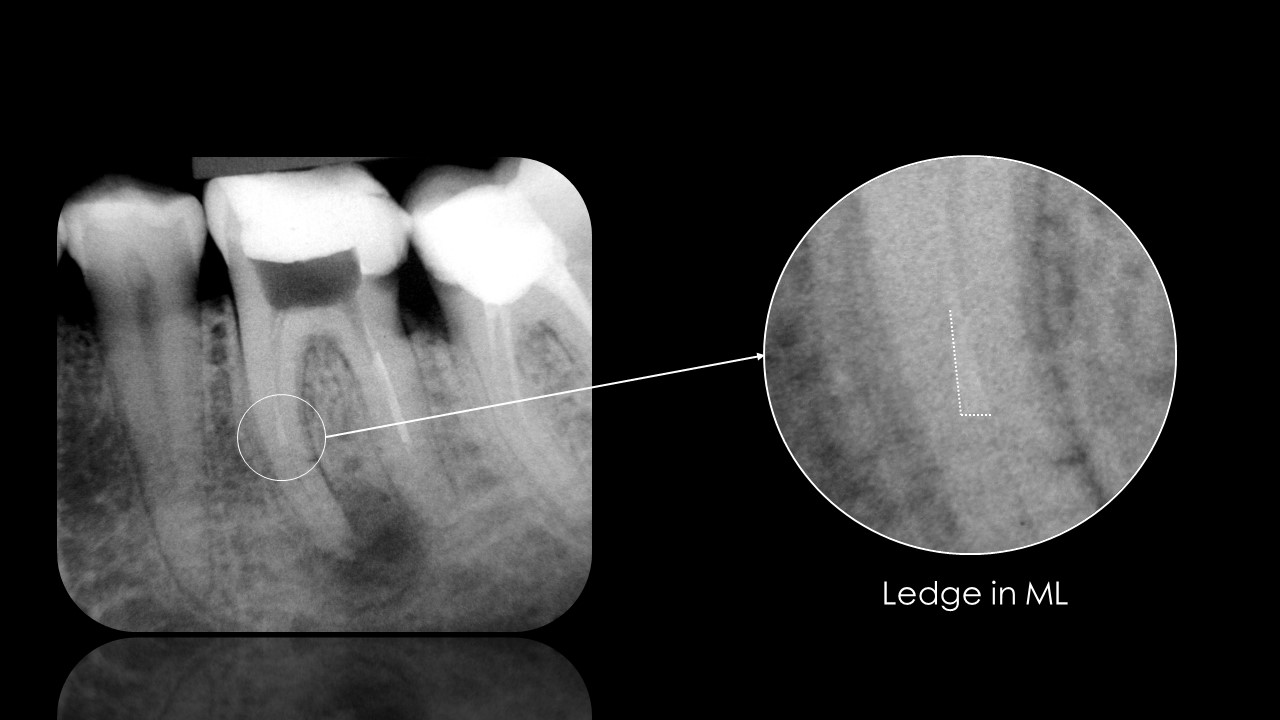

CBCT before endodontic therapy enables good planning and analysis with predictable outcomes. Especially helps in multi-rooted teeth, preventing from over-instrumentation, creating of ledge or separation of files.